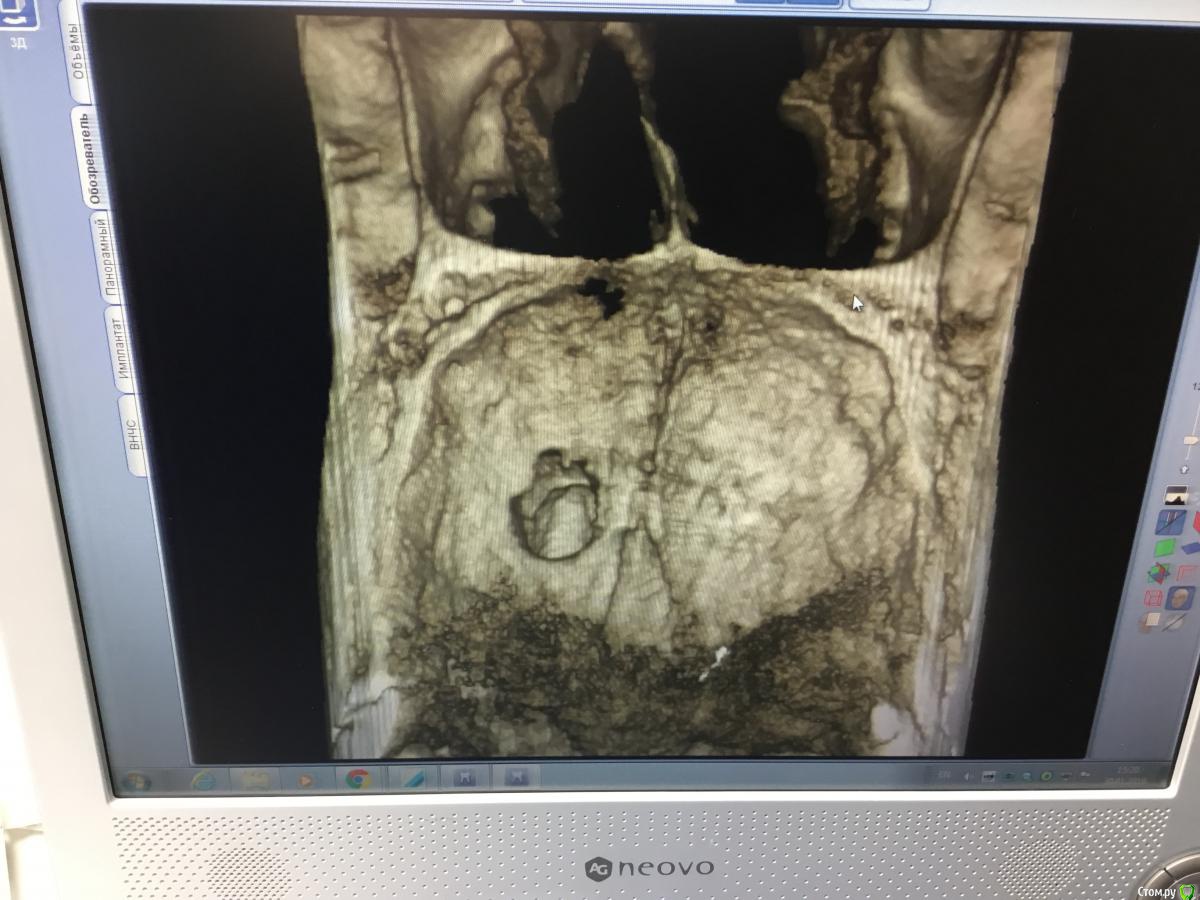

Zorrro Опубликовано 6 марта, 2016 Поделиться Опубликовано 6 марта, 2016 (изменено) Мой постоянный пациент привёл своего сынишку с жалобами на свищь на нёбе.Сделали кт и решили ,что вначале переберём каналы,а через пол года будем посмотреть куда нам двигаться дальше… Эстетика коронки на 11 вполне устраивала пациента,тем более он был уверен,что поставилимплант и вследствии коронку популярный доктор используя новейшие технологии и материалы,позволяющие не прибегать к устаревшим костным и ещё каким-то пластикам.запись к доктору уходила на пол года вперёд и молодой человек чудом втиснулся в этот плотный график,чтобы отхватить немножко и себе этих самых "новейших" технологий под нос. Фото ещё раз показывает,чтосамое главное в успехе частной практики это ВЕРА доктора в себя и то,что он делает.меня же коронка устраивала тем более,потому что переделывать её вместе с имплантом мне крайне не хотелось.обошлись комментарием про усиленную гигиену и регулярные наблюдения раз в пол года. итак занялись посильным трудом:отмыли 21 и 22,констрикция убежала за 50.02,остановились на 70.02 стальными файлами отступя 1мм,метапекс,через 2 недели irm и стекловолокно нафуджи+,филтек.договорились про контроль через пол года и коронки если всё ок. Ещё немного срезов до и преимущество кт перед прицельными снимкамиИ сразу после. Про коронки и корневой герметизм пациент не понял и решил оставить бломбы на месте. Изменено 6 марта, 2016 пользователем Zorrro 1 Ссылка на комментарий